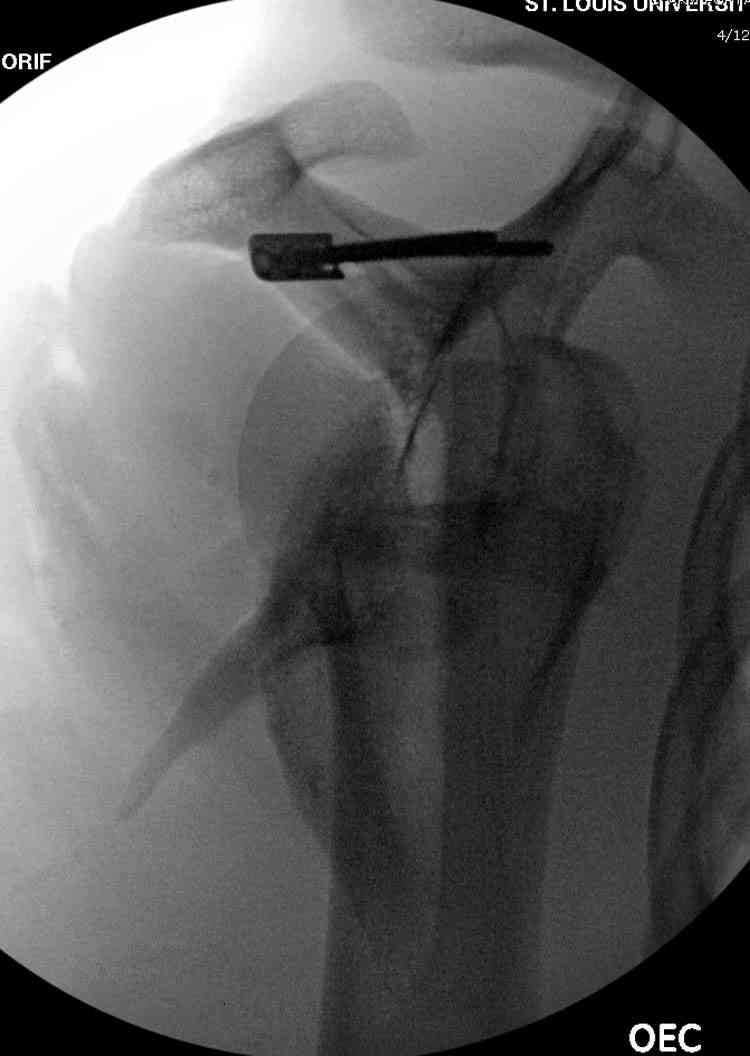

Никита, поздравляю с хорошей репозицией перелома

ключицы.

На какой срок решили оставить в аппарате, и что за аппарат? Разве аппарат Сушко не цилиндрический с движущимися пазами?

DK> На какой срок решили оставит в аппарате, и что за аппарат?

Планирую через четыре недели сделать рентген-контроль с решением вопроса об удалении АВФ. Аппарат смонтирован из деталей аппарата Илизарова. Картинки в приложении.

К сожалению оригинального аппарата Сушко нет в наличии (даже в глаза не видел), но использовался сам принцип метода по Сушко-Илизарову. Цитирую из "Основ по чрезкостному остеосинтезу аппаратом Г.И. Илизарова" (Л.Н.Соломин, 2005): 1. В каждый костный фрагмент должно быть введено не менее двух 2-мм консольных спиц, расположенных под углом к друг другу. 2. Места введения спиц должны располагаться вблизи суставных концов ключицы.

3. Точки введения спиц должны находиться на верхней поверхности ключицы.

4. Плоскость расположения спиц должна совпадать с продольной осью костных фрагментов.

5. При диафизарных переломах спицы проводят через оба кортикальных слоя.

6. При переломо-вывихах акромиального конца ключицы консольные спицы в акромиальный конец ключицы вводят только до упора в противолежащий

кортикальный слой; в акромиальный отросток лопатки консольные спицы не вводят, а используют спицу Киршнера "acr.,6-12", концы которой П-образно загибают навстречу друг другу.

7. Расстояние между поверхностью кожи и внешними опорами должно быть минимальным - в пределах 1,5-2 см.